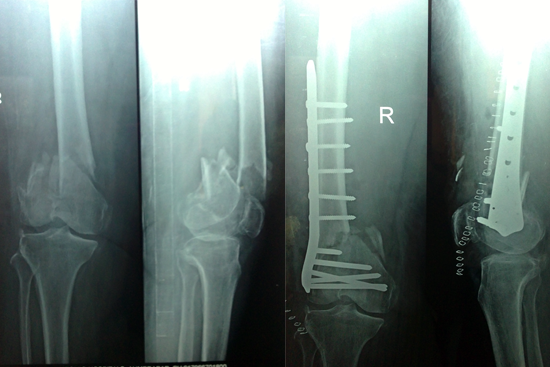

Non Union Femur

Case 1

Case 2 (Rampyari)